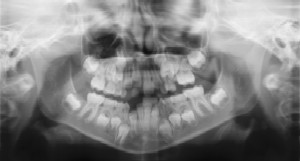

Dental Radiographs (X-Rays)

Radiographs (X-Rays) are a vital and necessary part of your child’s dental diagnostic process. Without them, certain dental conditions can and will be missed.

Radiographs detect much more than cavities. For example, radiographs may be needed to survey erupting teeth, diagnose bone diseases, evaluate the results of an injury, or plan orthodontic treatment. Radiographs allow dentists to diagnose and treat health conditions that cannot be detected during a clinical examination. If dental problems are found and treated early, dental care is more comfortable for your child and more affordable for you.

The American Academy of Pediatric Dentistry recommends radiographs and examinations every six months for children with a high risk of tooth decay. On average, most pediatric dentists request radiographs approximately once a year. Approximately every 3 years, it is a good idea to obtain a complete set of radiographs, either a panoramic and bitewings or periapicals and bitewings.